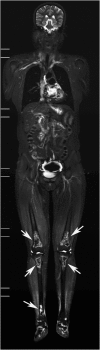

Results: STIR-WBMRI detected osteonecrosis in 15 (11.6%) patients. 38 joints were affected (mean, 2.5 per patient; range, 1-5 joints). Of the 38 joints affected by osteonecrosis, 33 had no clinical symptoms. Among the 12 patients who underwent regional MRI, STIR-WBMRI detected all 10 osteonecrotic sites seen on the regional MRI. The location, shape and size of the osteonecrotic lesions revealed on regional MRI were in accordance with those displayed on STIR-WBMRI. Of the 15 patients with osteonecrosis, 6 performed routine radiography of the affected joints and revealed no osteonecrotic lesions. Follow-up WBMRI detected new osteonecrosis in two patients whose first WBMRI revealed that there was no osteonecrosis in any skeleton.

Conclusion: In addition to displaying muscle inflammation, STIR-WBMRI can efficiently detect early multifocal osteonecrosis in the whole bodies of patients with PM/DM. Advances in knowledge: In patients with PM/DM, WBMRI which takes 12-15 min can display muscular involvement and detect early multisite osteonecrosis in the whole body at the same time. Osteonecrotic lesions revealed by WBMRI are in accordance with those displayed on regional WBMRI.